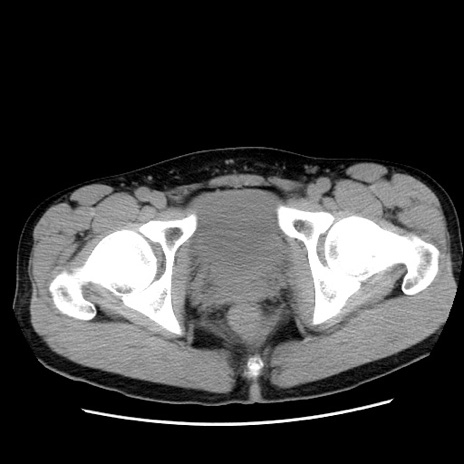

症例36(横断像)

【症例】20歳代 男性

【主訴】心窩部痛

【現病歴】今朝より上腹部痛あり。一旦軽快していたが再度出現したため救急要請。昨日夕に白身の魚を含む刺身を食べた。

【身体所見】BP 136/89mmHg、HR 74/min、BT 37.0℃、腹部:膨満、軟、心窩部に圧痛あり。反跳痛なし、筋性防御なし、腸雑音やや亢進あり。

【データ】WBC 17700、CRP 0.48